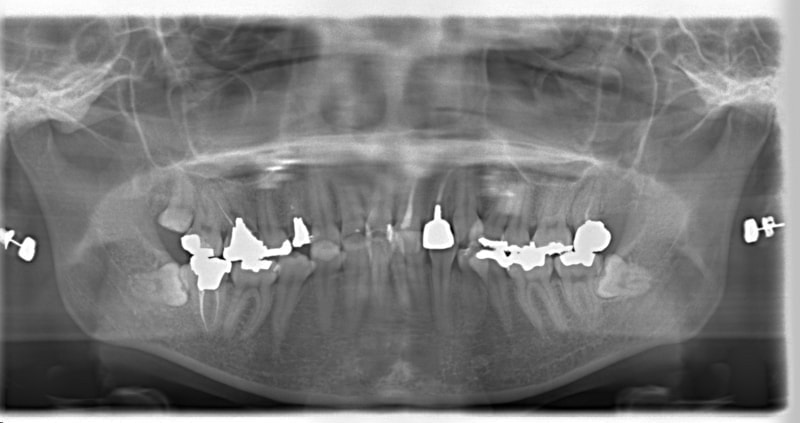

治療開始から1年8ヶ月後